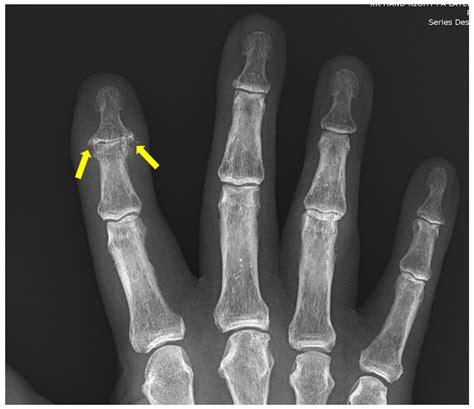

Experts Are Debating The Accuracy Of The Current Arthritic Index